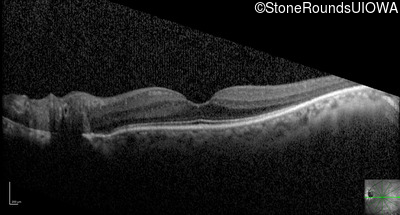

Optical Coherence Tomography - Right - 20/16 -1

Exemplar / OCT Stack